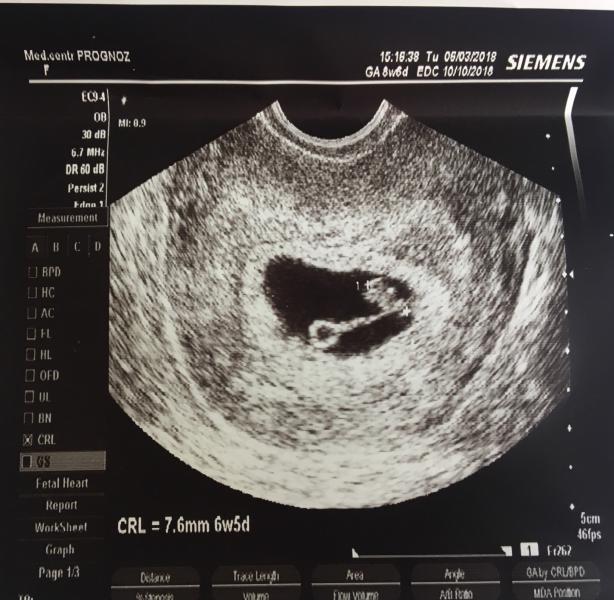

Похоже наш дом скоро снова посетит аист 🏡🐣🌱

Ну что тут сказать... чудеса случаются. 🌷 С мужем так рано не планировали второго ребёночка, хотели немножко попозже, но как говорится «мы предполагаем, а Бог располагает». 🌾

Вовку я кормлю грудью, с мужем всегда были аккуратны в сексе (все как всегда), и тут очередная задержка. Для меня это уже было привычным делом, на грудном вскармливании эти задержки достаточно частое явление. ✨Тут списались с врачом, подумали, что как обычно гормональный сбой. Но...